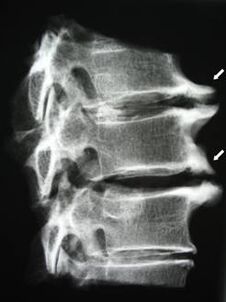

Hasierako faseetan, osteokondrosia detektatzen da MRI bidez. Geroago, patologia erradiografia erabiliz diagnostikatu daiteke. Trápaga bizkarrezurraren erradiografietan, ornoen arteko distantziaren murrizketa, giltzaduretako alderdietako aldaketa patologikoak eta osteofitosia nabaritzen dira.